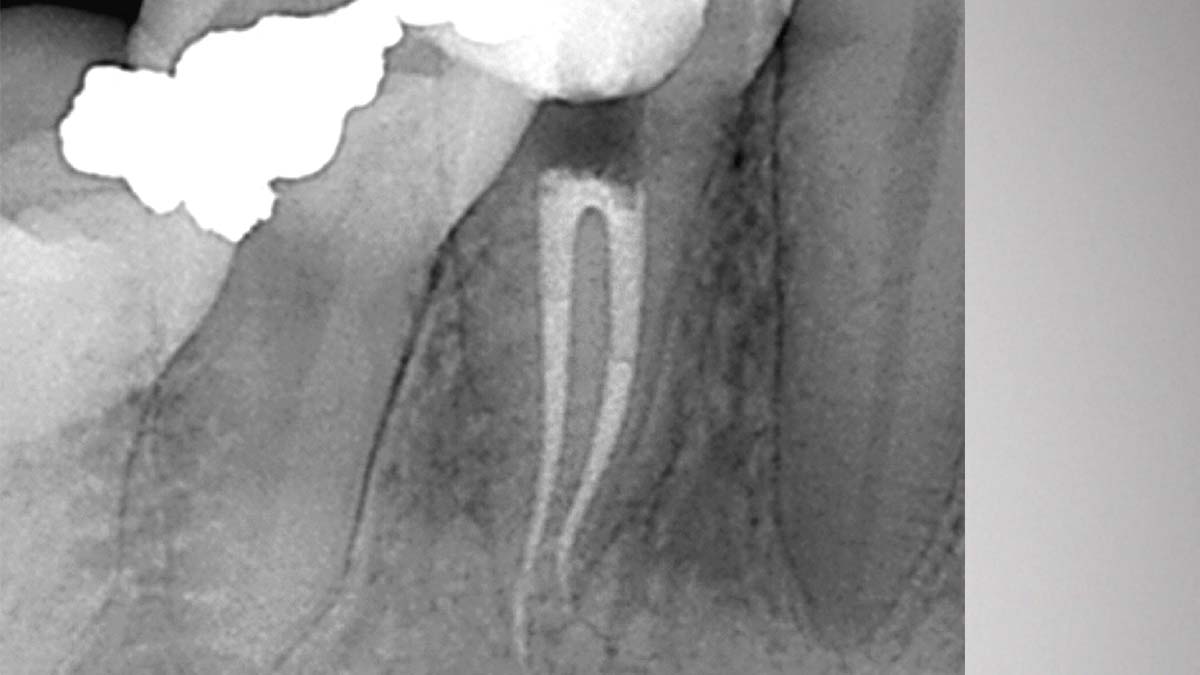

À gauche : l’utilisation de différentes formulations de gutta-percha dans un même cas peut entraîner différents degrés d’opacité.

Avec l’aimable autorisation du Dr Phillip Bell, Mooresville, NC

À droite : Gutta-Smart et Conform Fit utilisent la même gutta-percha avancée pour une cohérence radiographique.

Avec l’aimable autorisation du Dr Nathaniel Behrents, Fayetteville, AR